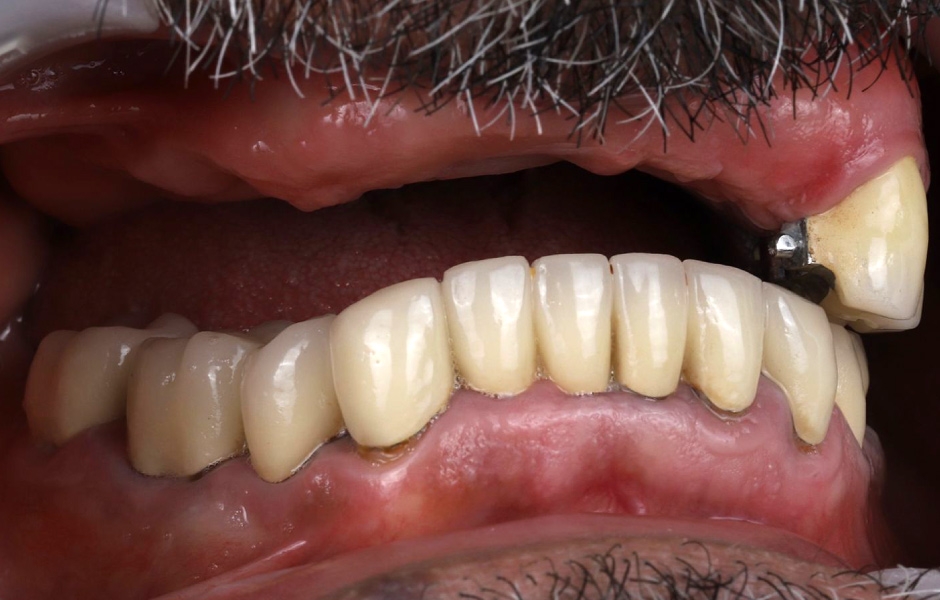

Při extraorální prohlídce nebyly zjištěny žádné významné abnormality. Pacient měl střední úroveň linie úsměvu (obr. 1–3). Po vyjmutí snímatelné náhrady byl odhalen můstek (obr. 4).

Intraorální vyšetření odhalilo starý můstek, který nahrazoval zuby 23 až 26 a zároveň sloužil ke kotvení částečné snímatelné náhrady s kovovou výztuží. Zuby 22 až 17 byly extrahovány již před delší dobou a alveolární hřeben v této oblasti byl zhojen. Nebyl přítomen plak ani zánět. Zuby vykazovaly mírnou až střední ztrátu attachmentu, ale nebyly pozorovány žádné parodontální léze nebo fraktury kořenů (obr. 5–8).

Obr. 1, 2

Obr. 3, 4